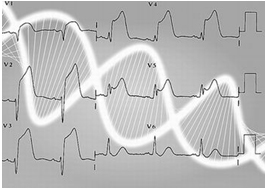

心電圖檢查

心電圖檢查心電圖是隱匿型冠心病診斷中最早、最常用和最基本的診斷方法,心電圖使用方便,易於普及,當患者病情變化時便可及時捕捉其變化情況,並能連續動態觀察和進行各種負荷試驗,以提高其診斷敏感性。無論是心絞痛或心肌梗塞,都有其典型的心電圖變化。

診斷主要根據靜息、動態或負荷試驗的心電圖檢查,放射性核素心肌顯像和(或)超聲心動圖的檢查,發現病人有心肌缺血的改變,而無其他原因解釋,又伴有動脈粥硬化的易患因素時,可考慮為隱匿型冠心病。進行選擇性冠狀動脈造影檢查或再加作冠脈內超聲檢查可確立診斷。我國學者最後修訂的心電圖運動負荷試驗心肌缺血的診斷標準是:

(一)心電圖活動平板或踏車分級運動試驗(次極量)判定心肌缺血的標準

符合下列情況之一者為陽性:

1、運動中出現典型心絞痛。

2、運動中及運動後呈水平型或下垂型(即缺血型)ST段壓低≥0.lmV。如果原ST段壓低者,運動後應在原基礎上再壓低0.lmV。

3、運動中血壓下降。

隱匿型冠心病的診斷1、運動中出現典型心絞痛或運動後心電圖改變符合下列條件之一者為陽性:

(1)在R波占優勢的導聯上,運動後出現水平型或下垂型別ST段壓低(ST段與R波頂點垂線的交角≥900),超過0.05mV,持續2分鐘者。如果原有ST 段壓低者,運動後在原有基礎上再壓低超過0.O5mV,持續2分鐘。

(2)在R波占優勢的導聯上,運動後出現ST段抬高(弓背向上型)超過0.2mV者。

2、運動後心電圖改變符合下列條件之一者為可疑陽性:

(1)在R波占優勢的導聯上,運動後出現水平型或下垂型ST段壓低0.O5mV或接近0.O5mV及QX/QT比例≥50%,持續2分鐘者。

(2)在R波占優勢的導聯上,運動後出現T波由直立變為倒置,持續2分鐘者。

(3)U波倒置者。

(4)運動後出現下列任何一種心律失常者:多源性室性早搏、陣發性室性心動過速、心房顫動或撲動、竇房阻滯、房室傳導阻滯(一、二、三度)、左束支阻滯或左束支分支阻滯、完全性右束支阻滯或室內阻滯。

此外,也有人提出運動後R波振幅增高(特別是在ST段壓低的導聯)也是心肌缺血的指標。